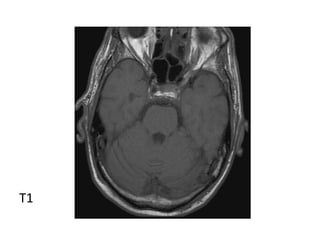

Hyperacute Infarct

T1